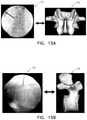

FIGS. 3A and 3B show a 3D CT image of a vertebra (FIG. 3A), as well as a 2D axial slice that is derived from the 3D CT image (FIG. 3B), as used in prior art techniques;

FIGS. 4A and 4B are schematic illustrations showing a C-arm being used to acquire an anteroposterior (“AP”) 2D radiographic image and a resultant AP image (FIG. 4A), and the C-arm being used to acquire a lateral 2D radiographic image and a resultant lateral image (FIG. 4B), as used in prior art techniques;

Reference is now made toFIGS. 3A and 3B, which are schematic illustrations of a 3D CT image of a vertebra (FIG. 3A), as well as a 2D axial slice that is derived from the 3D CT image (FIG. 3B), such images being used in prior art techniques. Reference is also made toFIGS. 4A and 4B, which show C-arm34 being used to acquire an anterior-posterior (“AP”) 2D radiographic image and a resultant AP image (FIG. 4A), and C-arm34 being used to acquire a lateral 2D radiographic image and a resultant lateral image (FIG. 4B), as used in prior art techniques.

As may be observed, the view of the vertebra that is important for determining the entry point, insertion direction, and insertion depth of the tool is shown in the axial 2D image slice ofFIG. 3B. By contrast, the 2D radiographic images that are acquired by the C-arm are summations of 3D space, and do not show cross-sectional views of the vertebra. Furthermore, due to the anatomy of the human body, such summations would not have been valuable if and when acquired from an axial angle (from the head, or from the toes) because it would not be possible to discern specifically the spinal portion being operated upon. As described hereinabove, Computer Aided Surgery (CAS) systems typically make use of CT and/or MRI images, generated before the subject has been placed in the operating room, or once the subject has been placed in the operating room but typically before an intervention has commenced. However, such procedures are typically more expensive than non-CAS procedures (such non-CAS procedures, including open procedures, mini-open procedures, and minimally-invasive procedures), limit tool selection to those fitted with location sensors as described above, and typically require such tools to be individually identified and calibrated at the beginning of each surgery.